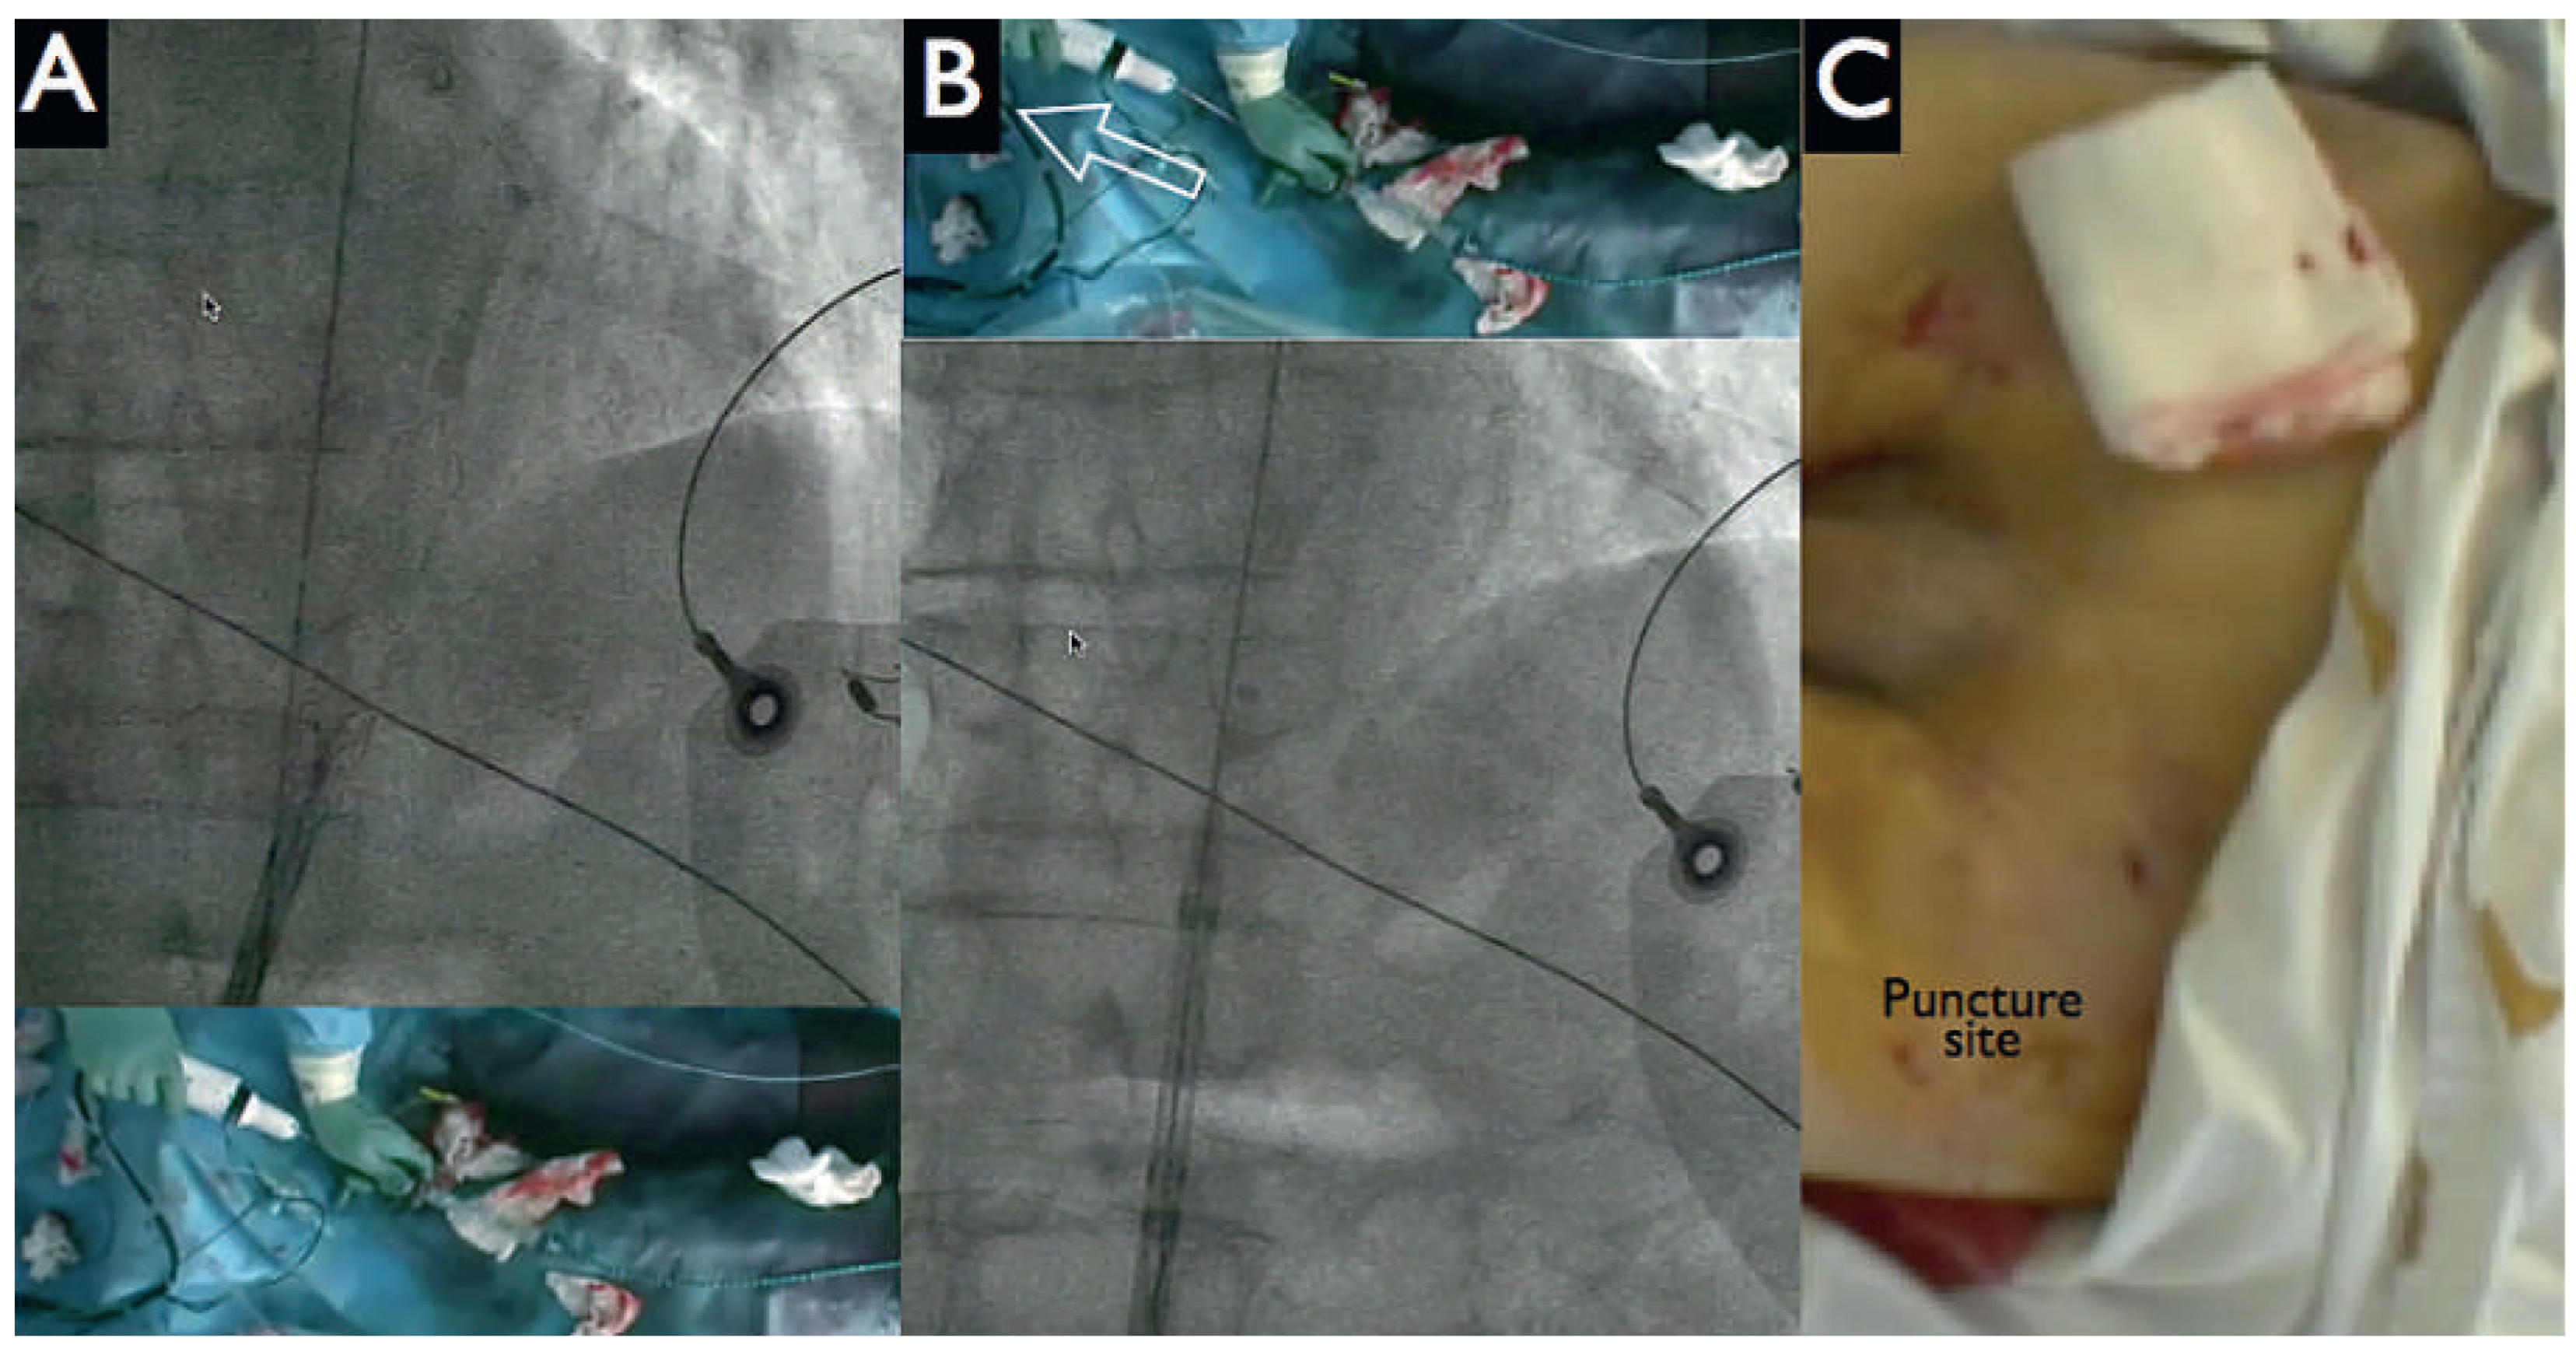

After the patient had given written informed consent, the decision to perform a HeartMate-PHP-assisted PCI was made. Both groins were used for vascular access. Following local anaesthesia, puncture of the left femoral artery under fluoroscopy (Figure 3 panel A) and preclosure of the left femoral with two Perclose devices were performed. Then, a 14 French (Fr) sheath was placed into the descending aorta. Systemic anticoagulation was achieved with administration of unfractionated heparin (70 U/kg); the patient had been pretreated with acetylsalicylic acid 100 mg/day. A 5 Fr JR4 catheter was positioned in the left ventricle and then exchanged over a 0.018 inch guidewire for the HeartMate-PHP catheter. The correct position of the device was verified by fluoroscopy by using a 5 Fr pigtail catheter from the right femoral artery as a marker of the aortic valve and the conduit was unsheathed up to its final 24 Fr size (Figure 3 panels B, C). Circulatory support was initiated at the minimum pump speed (approximately 1 l/min) and maintained throughout the intervention. Activated clotting time was kept at 250 s.

Figure 3. HeartMate-PHP implantation. Panel A: puncture of the left femoral artery under fluoroscopy. Panels B, C: Deployment of the HeartMate conduit by pulling out the covering sheath. Dashed line delineates the aortic valve.